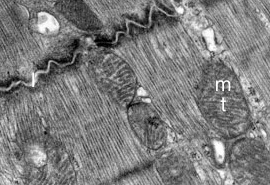

Las miofibrillas no presentan un empaquetamiento tan denso como las fibras musculares esqueléticas, dado que hileras de mitocondrias y de elementos longitudinales del retículo sarcoplásmico separan a los miofilamentos en haces paralelos anastomosados.

- Ver imagen☤ de microscopía electrónica de la organización de las miofibrillas.